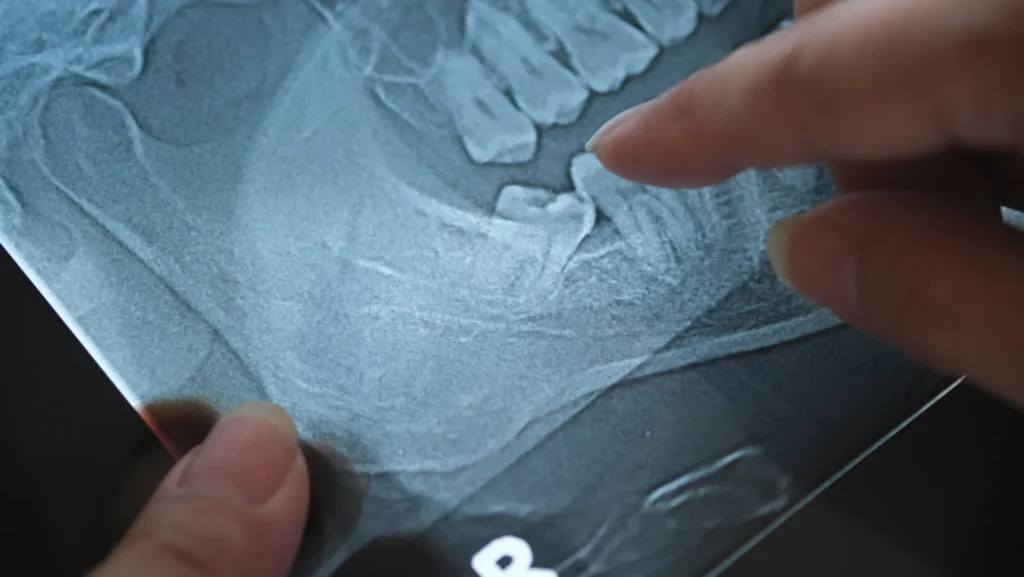

- Rimozione Cisti Orale: Diagnosi e asportazione di cisti mascellari e mandibolari per prevenire complicanze.

Quando l’osso è insufficiente, utilizziamo la tecnica Flusilift, la nostra metodologia innovativa per il rialzo del seno mascellare per via crestale, pianificata digitalmente. Questa è una forma avanzata della tecnica fluido-dinamica. Un fluido biocompatibile (acido ialuronico) solleva in modo controllato la membrana del seno mascellare, favorendo la rigenerazione ossea. Il tutto avviene senza incisioni estese, con minori tempi e disagi per il paziente. Questo procedimento permette di: